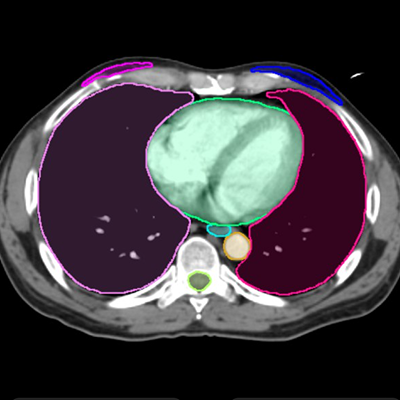

Lymph node level and OAR auto-contours ready for review in the TPS or MIM®. No clicks needed to launch.

Fully Automated Segmentation

Auto-Deploy and Export: Auto-contouring begins as soon as the patient is simulated. No import or export of contours necessary.